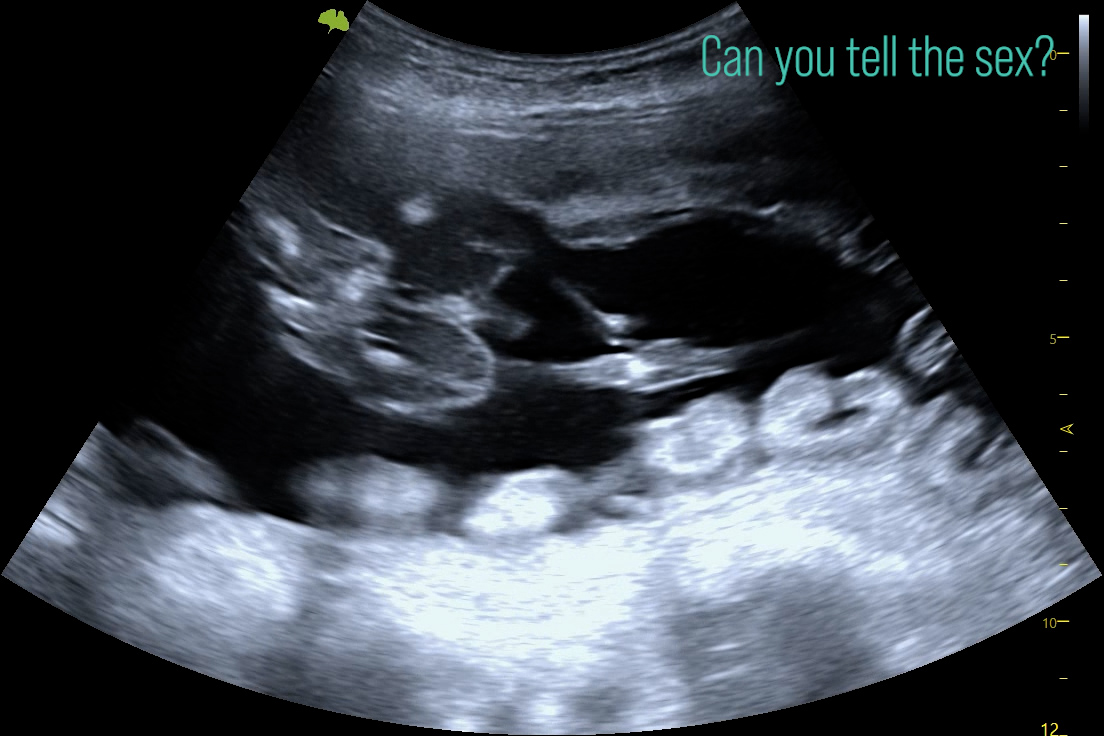

An AI-generated poster on foetal sexing in canines with ultrasound has recently been shared on social media. It advises completely the wrong time windows for sexing, depicts the umbilical cord